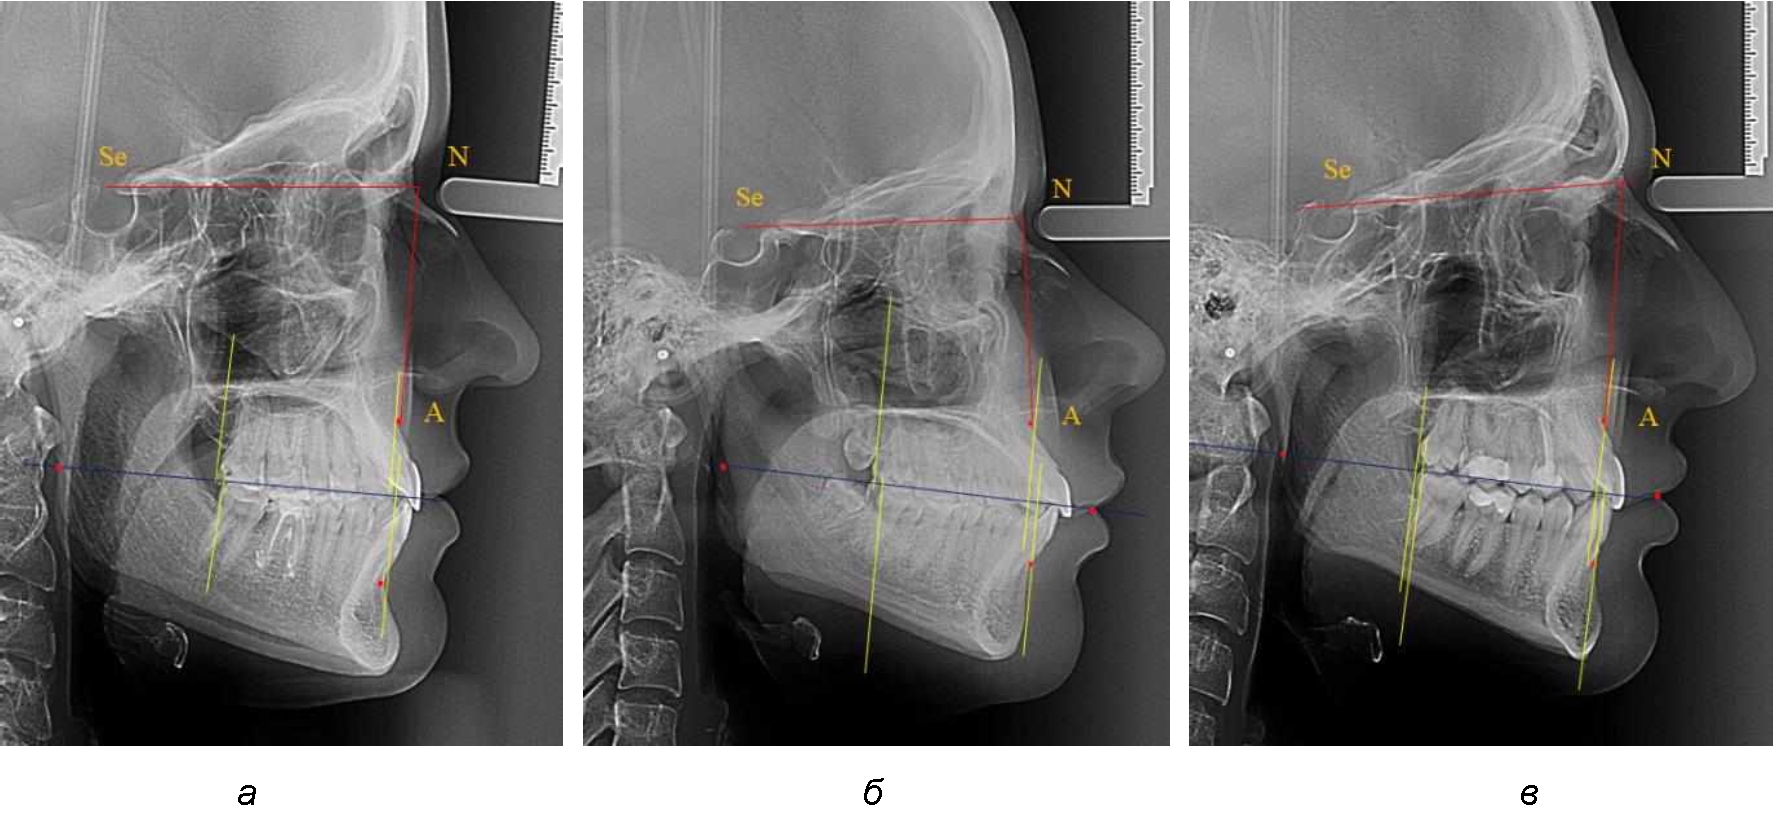

При сагиттальной патологии прикуса встречались варианты, при которых отмечалось равенство либо не равенство альвеолярно-ден-тальных размеров челюстей. Однако вне зависимости от этого, как правило, была отмечена разница в положении челюстей, измеряемая от конструируемой точки «rmРOcP» до точек апикальных базисов по Downs. С дистальной окклюзией было 20 снимков и с мезиальной окклюзией – 19 снимков.

Характерной особенностью мезиальной окклюзии было увеличение расстояния между проекционными апикальными точками, при котором существенно смещалась кпереди нижняя челюсть, а Wits-число имело отрицательные значения. Также дистальная точка нижнего моляра была расположена кпереди от верхней дистальной точки окклюзии второго моляра. Относительно равными считались показатели альвеолярно-дентальных размеров, при которых разница не превышала 1,5 мм. Тем не менее расстояние «rmРOcP-B(SM)» превышало расстояние «rmРOcP-A(SS)» в среднем по группе на (6,87 ± 1,62) мм, что свидетельствовало об аномалии положения челюстей, при котором визуально нижняя челюсть располагалась впереди верхней челюсти (рис. 3).

Рис. 3. Положение апикальных точек и челюстей при мезиальной окклюзии с равными (а) и разными (б) альвеолярно-дентальными размерами зубо-челюстных дуг

В тех случаях, когда при мезиальной окклюзии альвеолярно-дентальные размеры были различными, размер нижней челюсти превышал аналогичный параметр верхней челюсти в среднем на (3,74 ± 1,28) мм.

На рентенограммах с признаками дистальной окклюзии Wits-число имело положительные значения. Дистальная точка нижнего моляра была расположена позади верхней дистальной точки окклюзии второго моляра. Относительно равными, так же как и при анализе снимков с мезиальной окклюзией, считались показатели альвеолярно-дентальных размеров, при которых разница не превышала 1,5 мм. Тем не менее расстояние «rmРOcP-A(SS)» превышало расстояние «rmРOcP-B(SM)» в среднем по группе на (5,29 ± 1,47) мм (рис. 4).

Рис. 4. Положение апикальных точек и челюстей при дистальной окклюзии с равными (а) и разными (б) альвеолярно-дентальными размерами зубочелюстных дуг

В тех случаях, когда при дистальной окклюзии альвеолярно-дентальные размеры были различными, размер нижней челюсти превышал аналогичный параметр верхней челюсти, в среднем на (3,62 ± 1,12) мм.